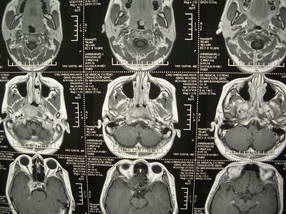

扫描示鼻咽腔不对称,中度狭窄,右侧咽隐窝消失,局部软组织肿块,鼻咽右侧壁增厚形成肿块,突入鼻咽腔,肿块平扫呈等密度,肿块向深部侵润,右侧翼内外肌受侵,右侧咽旁间隙变窄;向后生长,头长肌界线欠清,向后上生长侵犯同侧颈动脉鞘区。双侧海绵窦增宽,内见软组织影与鼻咽部肿块相连。考虑鼻咽癌。鼻咽癌主要是放射治疗,且效果较好;到当地有治疗设备较大医院治疗即可。

鼻咽部新生物(纤维血管瘤?鼻咽癌?)侵犯右侧中颅窝底及右侧海绵窦;建议必要时活检定性。

鼻咽部新生物侵犯右侧中颅窝底及右侧海绵窦,鼻咽癌可能性大。建议增强扫描。纤维血管瘤禁忌穿刺。